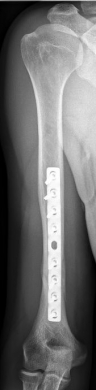

Oberarmschaftbruch1Oberarmschaftbruch2

Picture: Here you can see a completely shifted upper arm fracture with a strong bend of the axis. First the operative treatment was performed by repositioning the bone and internal splinting of the fracture with a medullary nail.